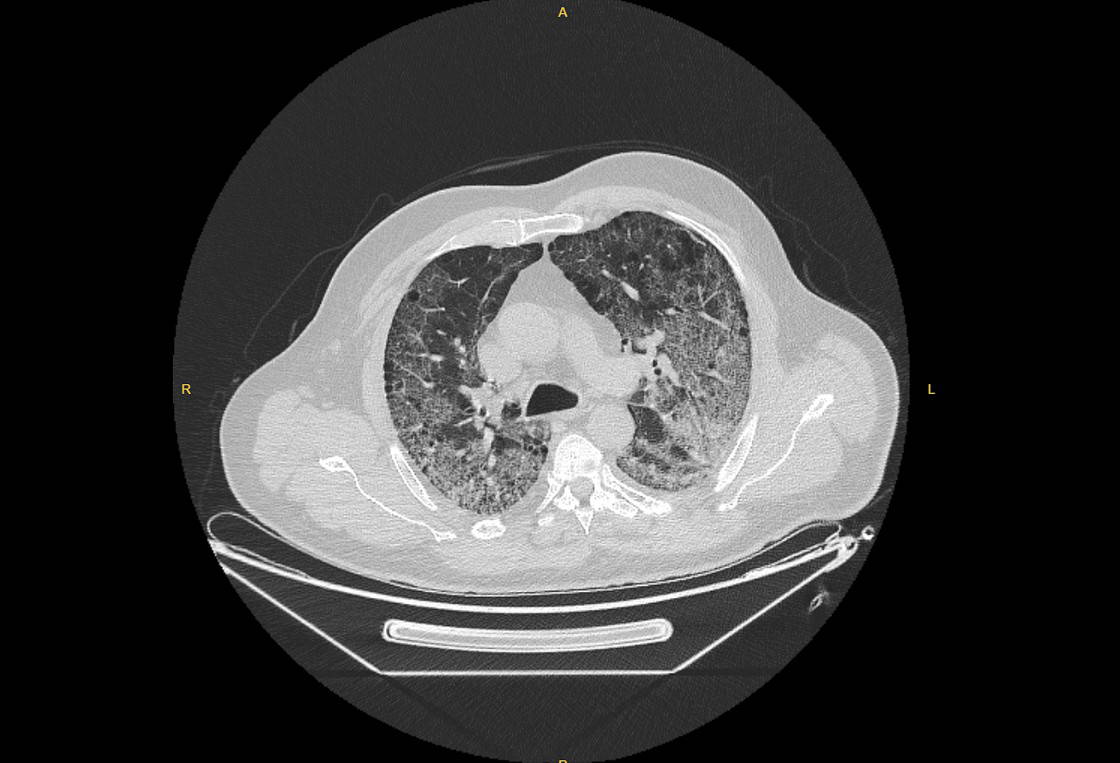

Prof. Dr. Karalezli, koronavirüs tedavisi gören hastalara ait akciğer görüntülerinden hastalığın yol açtığı tahribatı ve hastalar üzerindeki etkileri anlattı.

Tedavisine rağmen nefes darlığı şikayetleri devam eden bir hastaya uygulanan akciğer görüntülemesinde hastanın her iki akciğerinin büyük bir bölümünü enfeksiyon kapladığını tespit ettiklerini ifade eden Karalezli, "Bu hastalığın sonunun ne olduğunu bilmiyoruz. Akciğer tutulumları, bu şekilde olduğu zaman hastaları oksijen tedavisi ile gönderiyoruz. Çok yeni bir hastalık olduğu için bu seyir nasıl olacak? Geriye dönüş var mı? Takiplerle öğrenebileceğimiz bir durum." dedi.

Normal akciğer görüntüleri ile koronavirüs hastalarının akciğer görüntüleri arasında ciddi farklar bulunduğunu belirten Karalezli, şu bilgileri verdi:

"İnsanların aradaki farkları anlamaları için her iki akciğer görüntülerine de yer verdim. Görüntülerdeki beyazlıklar akciğerdeki tutulumu gösteren görüntüler ne yazık ki. Bu hastalar yoğun bakım hastaları. Filmler birbirine az çok benzeyen şekilde. Altta yatan hastalığı olanlarda ise daha kötü seyrediyor."

Kliniğe yeni başvuran bir hastanın, 5 Ağustos'ta çekilen tomografi görüntülerindeki tipik koronavirüs görüntülerinin olduğunu ifade eden Karalezli, hastanın bir hafta içerisindeki tomografi görüntüsünde ciddi değişiklik olduğunu ve enfeksiyonun çok arttığını söyledi.